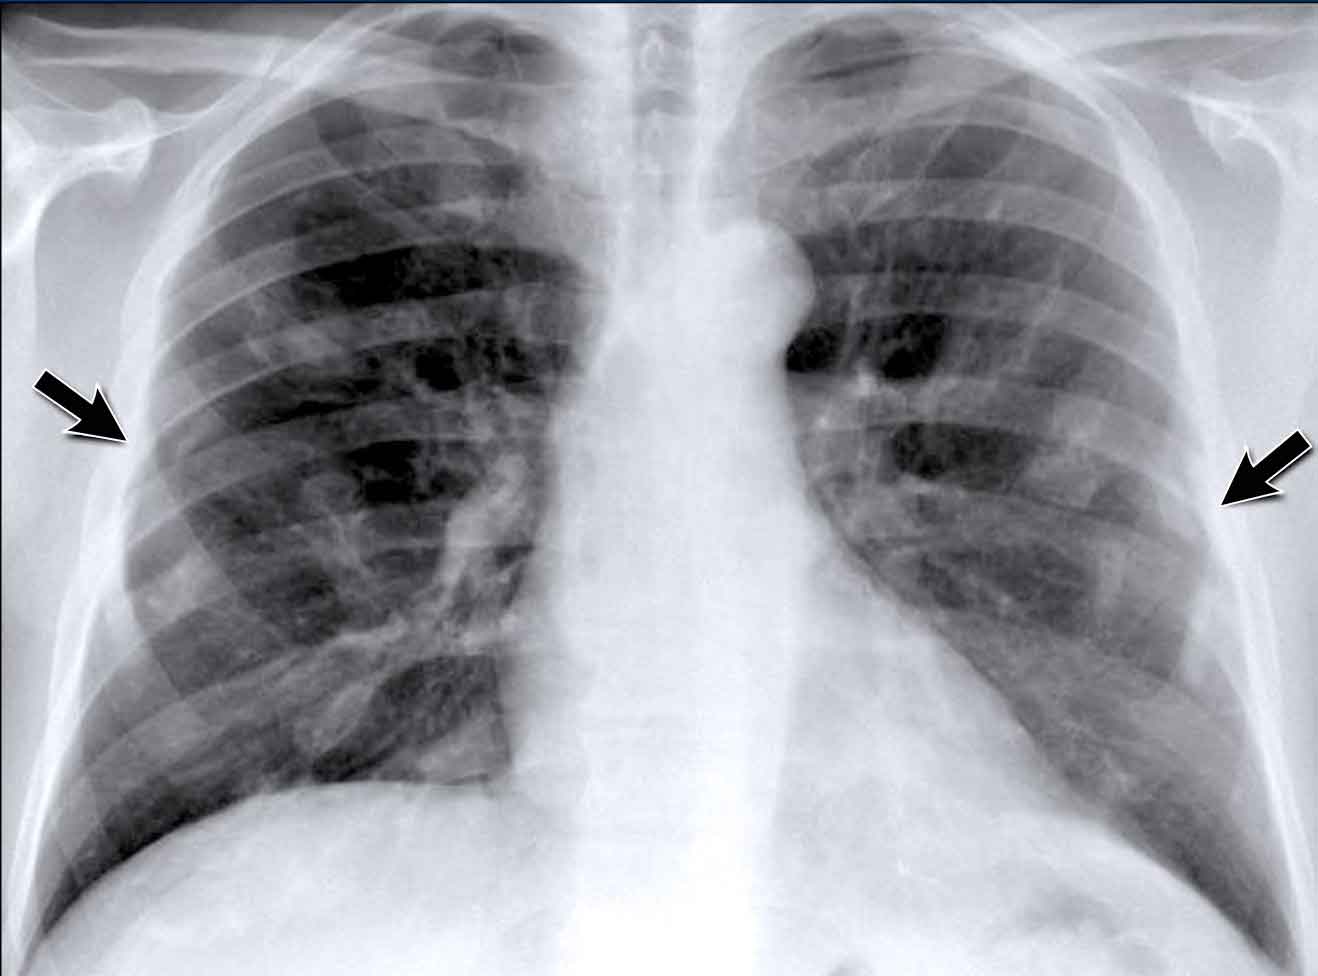

Case Example: Subtle Signs of Congestive Heart Failure

Begin by reviewing these current chest radiographs.

Based solely on these images, one might suspect congestive heart failure (CHF), though the findings are subtle.

Now review the previous study…

Scrolling between the current and prior films significantly increases diagnostic confidence in your diagnosis of congestive heart failure.

Key comparative findings include:

• Cardiac size: Slightly increased compared to the previous study; however, cardiomegaly was already present.

• Pulmonary vasculature: Mild vascular engorgement suggesting elevated pulmonary venous pressure.

• Interstitial markings: Subtle signs of interstitial edema .

• Pleural effusions: Bilateral small effusions, with subtle changes in the inferoposterior borders of the lower lobes, suggesting fluid accumulation.